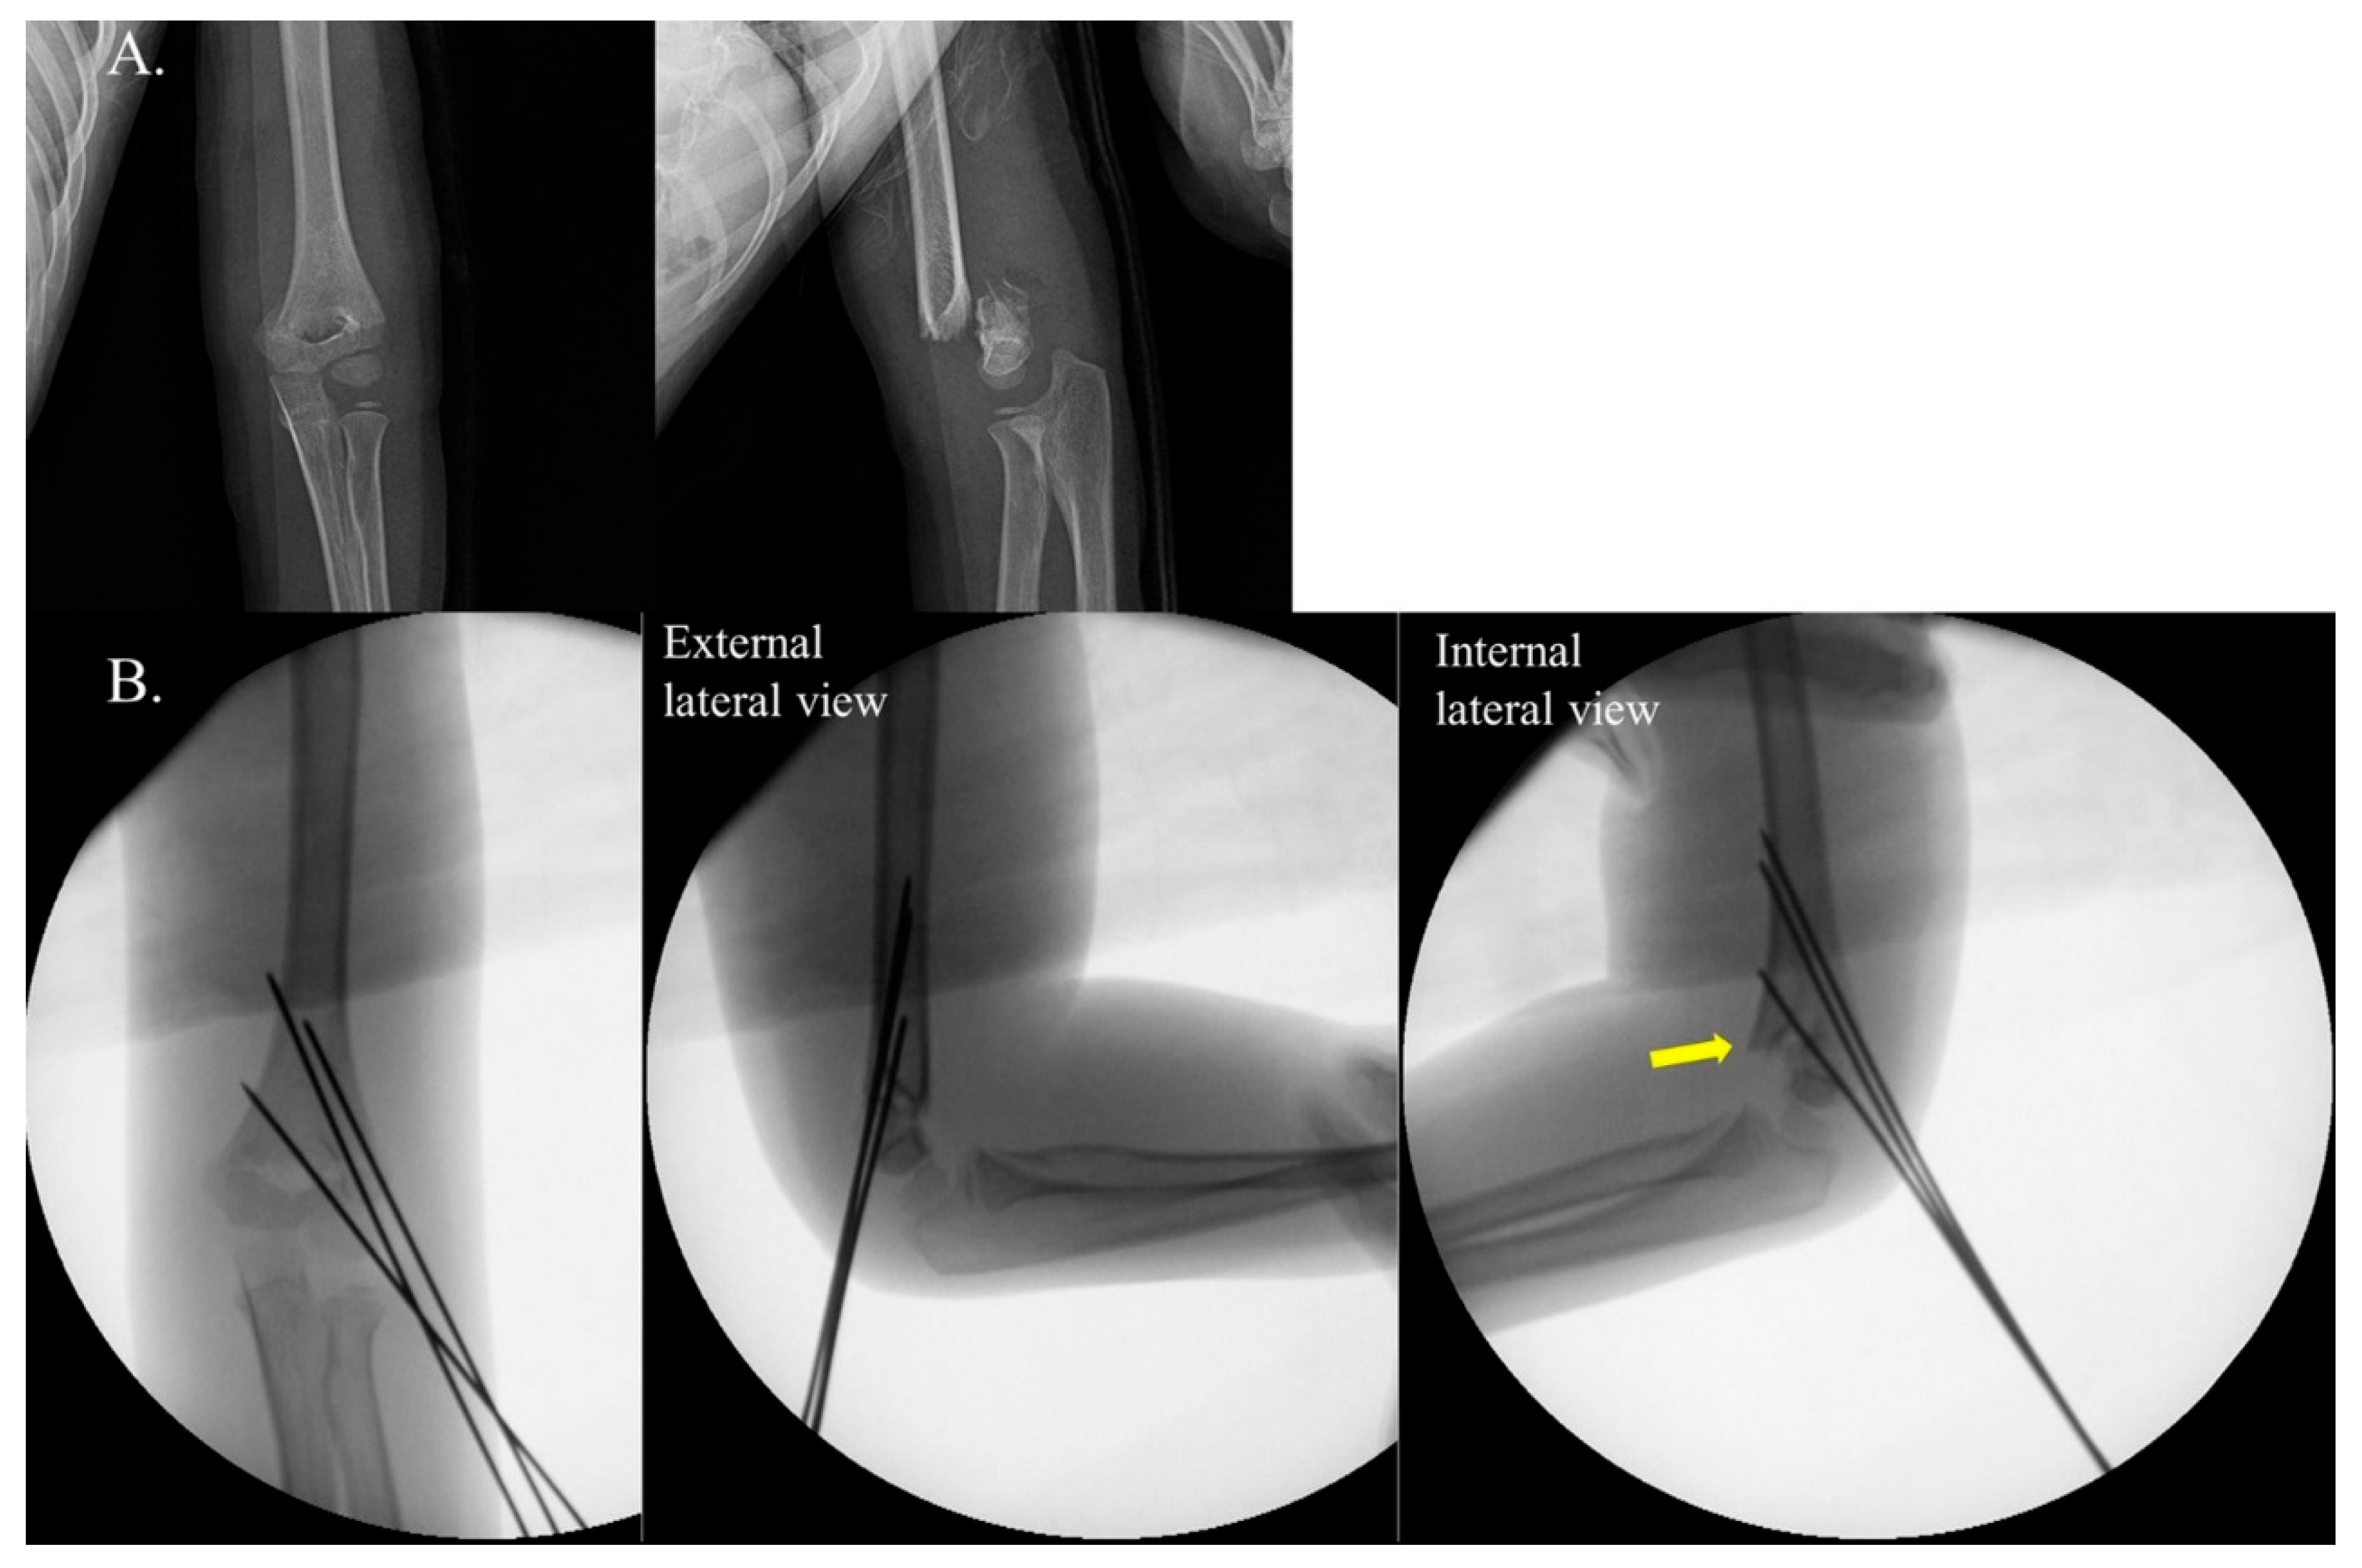

Figure 2. Example of negative internal rotational stress test (IRST) results in a 9-year-old boy with a Gartland type III supracondylar fracture. Panel (A) shows the preoperative radiographs. Panel (B) depicts C-arm images demonstrating a negative IRST. Good bone contact and well-maintained reduction are observed in both the anteroposterior (AP) and external lateral views. Notably, the reduction was maintained even in the internal stress lateral view.